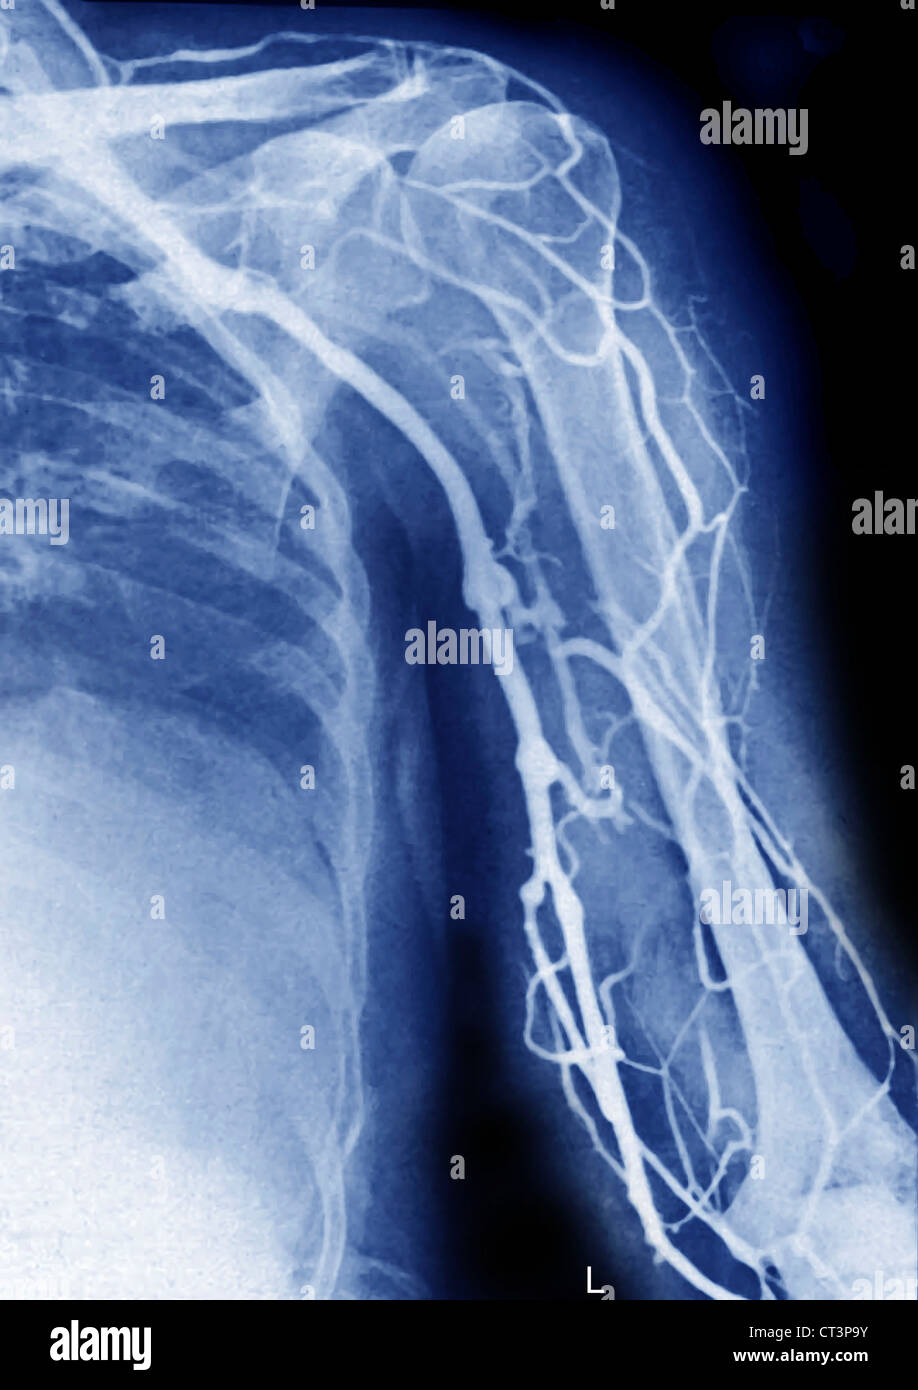

RMJE7CWP–Der Plexus brachialis ist ein Nervennetz im Nacken- und Schulterbereich, das für die motorischen und sensorischen Funktionen der oberen Extremität von wesentlicher Bedeutung ist. Das Bild zeigt den Plexus brachialis an seiner anatomischen Position.

RFEW9HG6–Oberflächlichen Lymphgefäße der oberen Extremität, graviert Vintage Illustration. Üblichen Medizin Wörterbuch - Paul Labarthe - 1885

RFEW91T9–Oberflächlichen Lymphgefäße der oberen Extremität, graviert Vintage Illustration. Üblichen Medizin Wörterbuch - Paul Labarthe - 1885